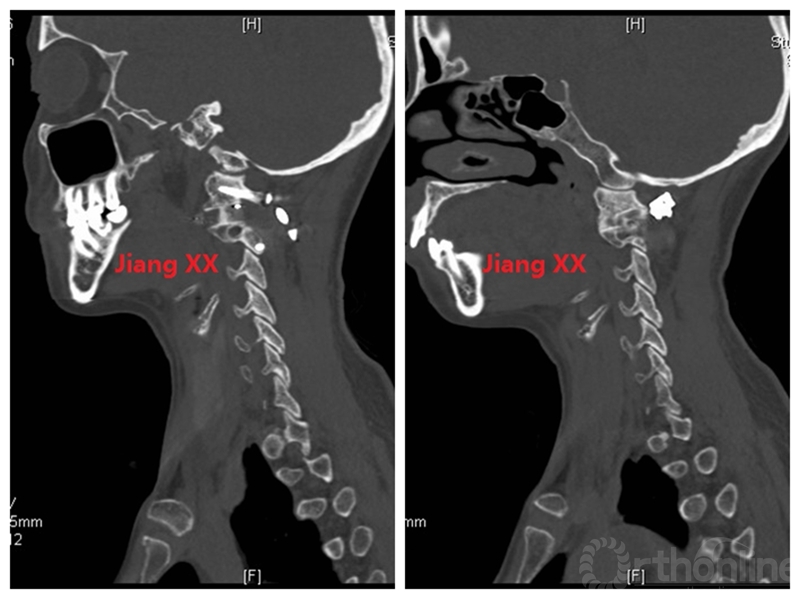

术后X线

术后一年CT